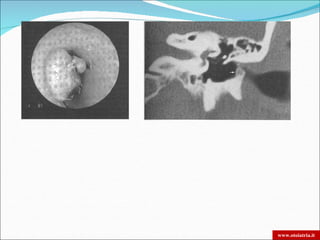

ESOSTOSI                                              OSTEOMI

•Proliferazione di osso compatto            ISTOLOGIA    •Grandi canali fibrovascolari di Havers

lamellare, avascolare, ricoperta da pelle                circondati da osso lamellare

sana                                                     spongioso e tessuto fibroso.

•Larga base di impianto                                  •Peduncolati

Porzione ossea del CUE (anteriore e/o          SEDE      Sutura timpano-squamosa o timpano-

posteriore)                                              mastoidea

Multiple e bilaterali                        NUMERO      Solitari e monolaterali

Poco opachi                                    RX        Molto opachi

Azione termica e meccanica dell’acqua        FATTORI                        ?

fredda sulla osteogenesi                    FAVORENTI

Compressione ischemia (cuffie)

Fattori intrinseci: Razza (bianca), sesso      ETIO-                        ?

(M), ereditarietà                           PATOGENESI

Fattori estrinseci: Acqua

Multiple lesioni

A larga base di impianto

Corticale intatta

ESOSTOSI

Lesione unica

Pedunculata

Unilaterale

Assenza di invasione corticale

OSTEOMA